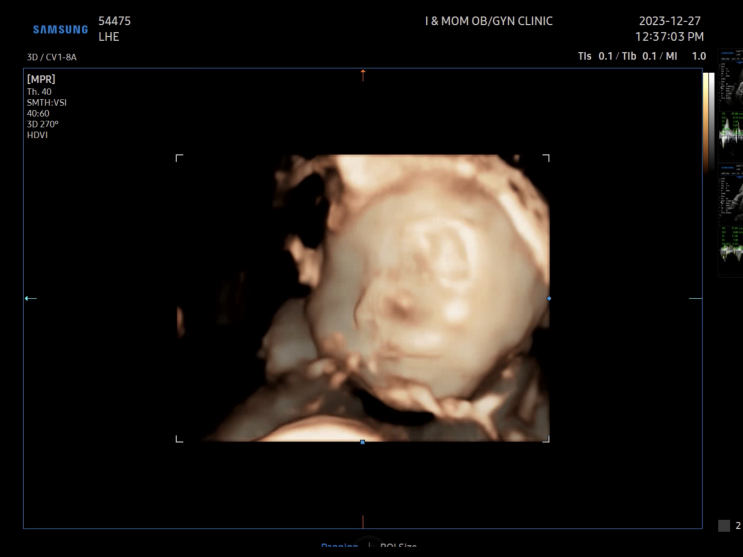

??쌍둥이 임신 28주 태아 크기차이 양수차이 경부길이 짧음 | 강릉아산병원 응급실 입원

#쌍둥이임신28주차 1/10(수) 강릉 아이앤맘 정기검진 26주차 임당검사 27주차 재검통과 그리고 또 한주만에...